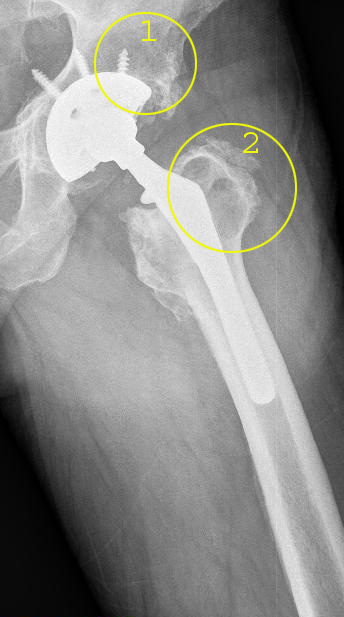

Bei der Prothesenplanung ist es für ein dauerhaft gutes Ergebnis entscheidend, die Pfannengröße und Schaftlänge optimal auf die anatomischen Gegebenheiten des Patienten anzupassen. Das Röntgenbild der Hüftprothese zeigt ein mechanisches Problem, das zu einer frühen Lockerung geführt hat: Die Schaftlänge wurde hier nicht optimal gewählt und der Zementmantel um die Prothese ist nicht ganz gleichmäßig. Der Oberschenkelknochen zeigt in der Höhe des Trochanters, einem seitlichen Knochenvorsprung des Oberschenkelknochens (Markierung 1), eine deutlich verminderte Knochendichte. Die Tragfähigkeit des Femurs (Oberschenkelknochen) ist also bereits vermindert. Der zementierte Prothesenschaft hat sich aufgrund der ungünstigen Geometrie gelockert und ist im Markraum des Oberschenkels verkippt. Eine schmerzhafte Sinterung (Einsinken der Prothese in den Oberschenkel) mit Beinlängenverkürzung ist die Folge. Der Patient konnte ohne Gehhilfe nicht mehr gehen. Seine maximale Gehstrecke war infolge der gelockerten Hüftprothese stark eingeschränkt.

Für die Wechseloperation wurde eine Prothese mit einem einwachsendem Langschaft, der tief im Oberschenkelknochen verankert ist, gewählt. Dies entlastet den geschwächten Trochanter (seitlicher Knochenvorsprung des Oberschenkelknochens). Tiefere Anteile des Oberschenkels beteiligen sich an der Last. Keramischer Ersatzknochen verstärkt die Knochenbildung am Trochanter, damit sich die Knochensubstanz in diesem Bereich wieder regeneriert. Der Patient war nach der Wechseloperation wieder beschwerdefrei.